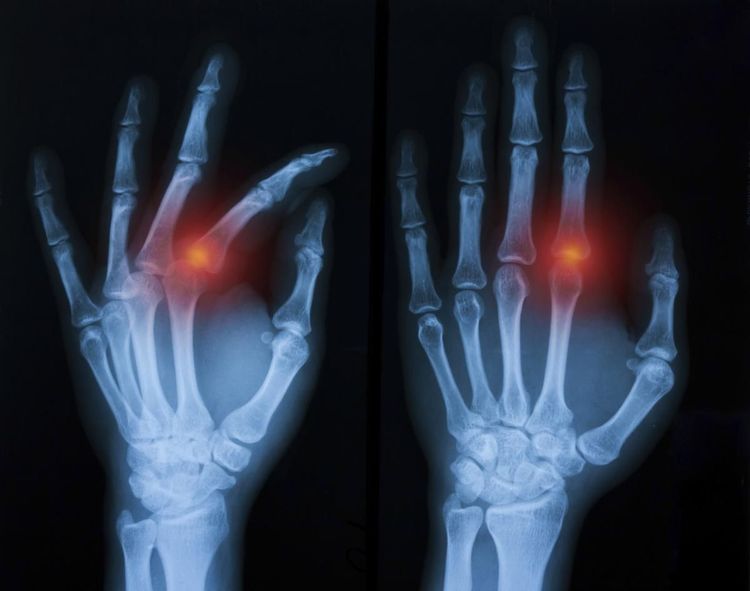

Pathological Fracture - आजारामुळे हाडे कमजोर होऊन तुटणे.

Stress Fracture - विशिष्ट भागावर नेहमी दबाव किंवा ताण पडून तुटणे. हे फ्रॅक्चर खेळाडूंमध्ये जास्त आढळून येते.